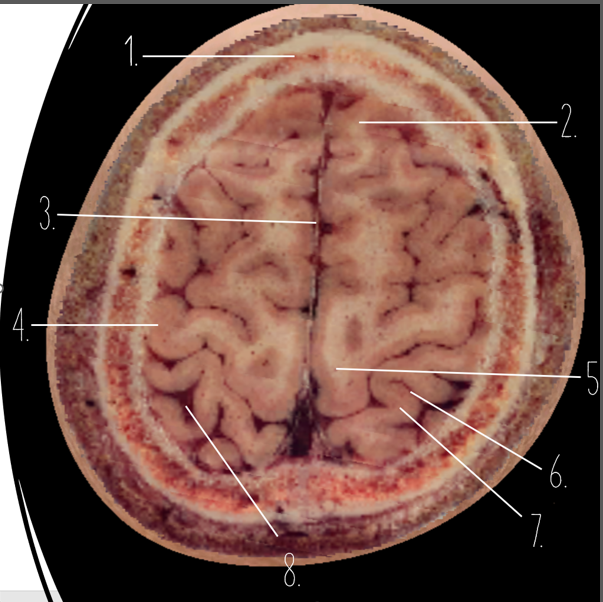

Brain Cross Sectional

1

Frontal Bone

2

Frontal Lobe

3?

Falx Cerebri

4?

Gray Matter

5?

White Matter

6?

Sulcus

7?

Gyrus

8?

Fissure